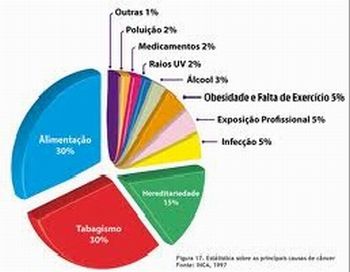

· Quais são as causas externas ou fatores de risco de natureza ambiental do câncer?

Sugerimos também que reforce a importância de se conhecer os fatores de risco ambientais para a prevenção do câncer. Não se deverá aprofundar neste momento a fundamentação teórica sobre estes fatores, mas aguçar a curiosidade dos alunos para que busquem aprofundamento dessas informações, em pesquisas na internet e socialização, por meio de seminários no Módulo 3.

· Quais são os principais fatores que aumentam o risco de câncer?

· Quais são os alimentos que aumentam o risco de câncer?